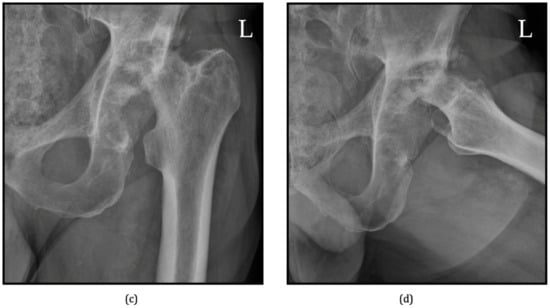

6.1. Radiographs

- Flemming, D.J.; Gustas-French, C.N. Rapidly progressive osteoarthritis: A review of the clinical and radiologic presentation. Curr. Rheumatol. Rep. 2017, 19, 42. [Google Scholar] [CrossRef]

- Zazgyva, A.; Gurzu, S.; Gergely, I.; Jung, I.; Roman, C.O.; Pop, T.S. Clinico-radiological diagnosis and grading of rapidly progressive osteoarthritis of the hip. Medicine 2017, 96, e6395. [Google Scholar] [CrossRef]

- Chau, H.T.H.; Wong, P.Y.; Pan, N.Y.; Ma, K.F.J. Rapidly destructive hip osteoarthritis: A diagnosis not to miss. Br. J. Radiol. 2024, 97, 1526–1533. [Google Scholar] [CrossRef]